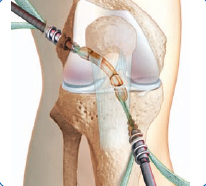

Ҷарроҳии артроскопии пайванди салибмонанди буғуми зону